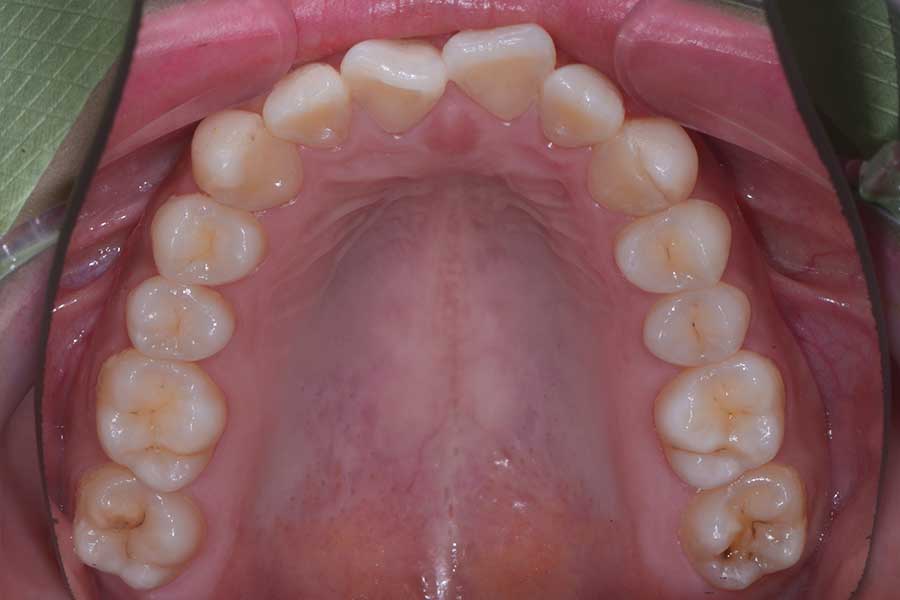

【20代女性】前歯の形と並びを良くしたい

治療前

治療後

主訴 前歯の形と並びを良くしたい

期間 12か月

費用 治療費70万(別途調整料)

デンタルローン65回 ¥12500/月

治療内容 上下顎リンガル矯正(裏側矯正)

治療に伴うリスク 後戻り